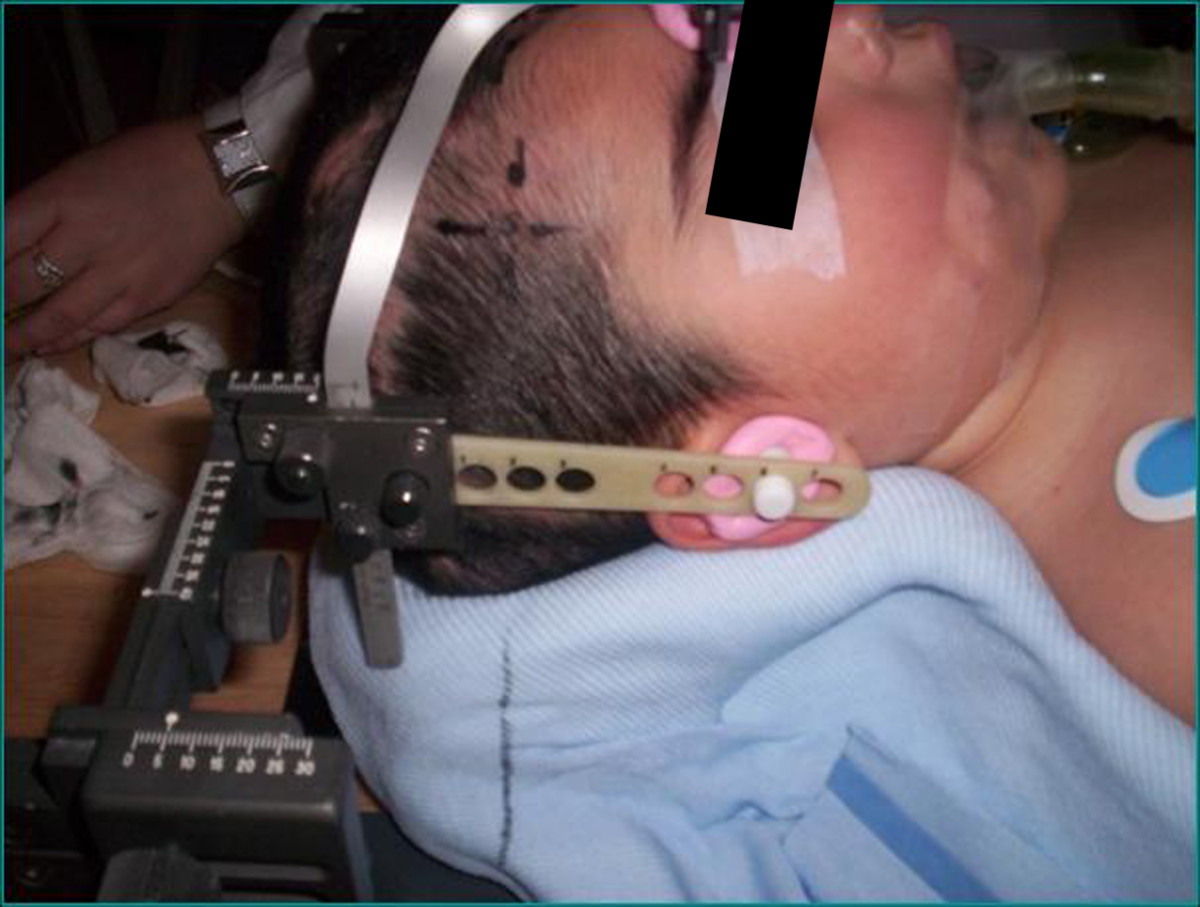

Individual immobilization was employed in all cases. Depending on the site of the treatment, a customized alpha-cradle mould was used for thoracic and abdominopelvic tumor sites, whereas a 'home-made' non-invasive stereotactic frame system was used for head and neck tumors (Figure 1).

Figure 1. "Home-made" non-invasive stereotactic frame.